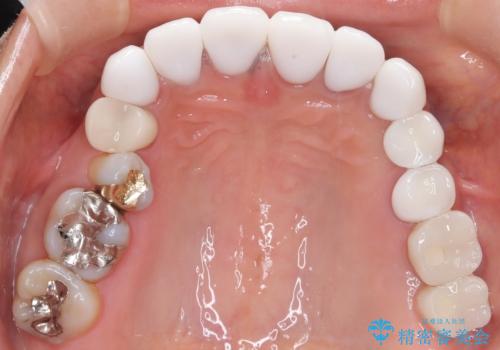

【オールセラミッククラウン】前歯を白くきれいにしたい。

- 前歯の変色を主訴に来院されました。

歯茎のラインも整っていなかったため、手術を行いきれいな被せ物をいれることができました。

歯茎のラインを整える手術を行ったあとは、しばらく待ってから被せ物の治療を行っていきます。